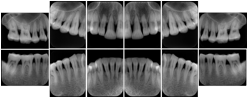

6 Standard + 4 Bitewing C Dental Image Layout

DL-P002E

Reference:

01

Standard

11, 12, 21, 22

11

32, 31, 41, 42

20

Bitewing

18, 17, 16, 15, 48, 47, 46, 45

21

17, 16, 15, 14 47, 46, 45, 44

23

27, 26, 25, 24, 37, 36, 35, 34

24

28, 27, 26, 25, 38, 37, 36, 35